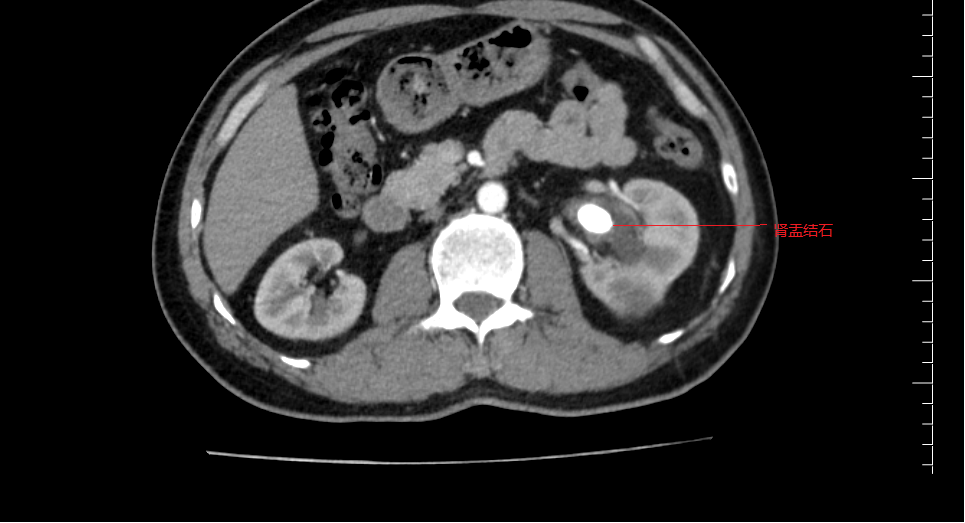

本以为是普通的腰疼,没想到检查发现左肾里竟同时藏着“结石”和“大囊肿”两个隐患。近日,一名47岁的男性患者在阳山县人民医院泌尿外科接受了左输尿管软镜下钬激光碎石取石术,同时通过经尿道输尿管软镜下肾囊肿内切开引流术,一次手术解决了两个棘手问题。术后患者恢复迅速,已顺利出院。 体检发现“双雷”埋伏 47岁的张先生(化名)最近因腰部不适来我院就诊。原本以为只是劳累所致,没想到B超和CT检查结果却让他大吃一惊:他的左肾不仅有多发结石,还长了一个巨大的肾囊肿。 这种情况在临床上并不少见,但同时处理起来却颇为棘手。泌尿外科医生介绍,传统的治疗方案往往需要“分步走”:要么先通过经皮肾镜(在腰上打孔)处理结石,后期再处理囊肿;要么通过腹腔镜手术“剥”掉囊肿,但对结石却难以兼顾。这意味着患者可能要经历两次手术、两次麻醉,不仅身体创伤大,恢复周期长,也增加患者经济负担。 巧妙设计:“借道”尿道,一箭双雕 考虑到患者年仅47岁,对生活质量要求高,且非常希望避免在身体上留下多处疤痕,我院泌尿外科团队经过详细的术前讨论,决定为其实施输尿管软镜下的一期手术。 这个手术的奥妙在于“借道而行”。医生利用人体天然的泌尿系统腔道——尿道,将纤细灵巧的输尿管软镜送入肾脏。 1. 先碎石: 抵达左肾后,医生首先发现了那些“捣乱”的结石。通过软镜的工作通道,插入钬激光光纤,将结石精准击碎成粉末状或小碎片,较大的碎片可直接用套石篮取出 。 2. 后开窗: 碎石完成后,镜头一转,找到了那个压迫肾实质的囊肿。在软镜的直视下,医生换用钬激光在囊肿壁最薄、最靠近肾集合系统的位置切开一个“小窗”,让囊液能够顺畅地流入肾盂,顺着尿液排出体外,从而达到内引流减压的目的 。 就这样,一根软镜,两种操作,患者腰上的两颗“雷”被一次性安全拆除。 微创领域的“黑科技” 输尿管软镜技术被誉为泌尿外科医生的“第三只眼”。其头端可以 270度弯曲,能轻松到达肾脏的各个角落,处理传统硬镜无法触及的结石和病变 。 而将其应用于肾囊肿内切开引流,更是近年来微创理念的延伸。相比于传统的腹腔镜或开放手术,这种术式拥有无可比拟的优势 : 真正无痕: 手术完全经自然腔道进行,体表没有任何切口,满足了现代患者对美观的需求。 同期治疗: 如张先生这般,可以一次麻醉处理多个合并疾病,避免了二次住院的麻烦。 恢复迅速: 由于手术创伤极小,患者术后疼痛轻。文献数据显示,此类手术患者术后住院天数通常仅为3天左右 。张先生术后恢复顺利,很快便康复出院。 术后康复与新生活的开始 术后,张先生的腰部胀痛感明显缓解。复查显示,左肾结石已清理干净,囊肿也已成功“瘪”了下去。他感慨地说:“原本以为要在身上打两个洞,甚至做两次手术,没想到睡一觉起来,两个问题都解决了,身上连个创可贴都没贴。” 此次手术的成功,标志着我院泌尿外科在处理肾脏复合性疾病方面迈上了新台阶。我们也将继续探索和运用更先进的微创技术,让更多的患者能享受到“损伤小、恢复快、效果佳”的优质医疗服务。 门诊地址:门诊楼2楼泌尿外科诊室 住院部地址:外科楼(5号楼)9楼 联系电话:0763-7816525 杨竞锋 主任医师 阳山县人民医院泌尿外科主任,主任医师。广州医科大学临床医学专业毕业,1993年7月参加工作。从事大外科临床工作10余年,泌尿外科专科工作10余年。曾多次在广州市三甲医院进修泌尿外科专业。擅长尿路结石及良性前列腺增生微创治疗,熟练开展前列腺整体剜除术等四级手术,临床经验丰富。现任清远市医学会泌尿外科分会常务委员,清远市医学会男科分会委员,广东省泌尿生殖尿控分会委员。曾主持市级课题2项,以第一作者或通讯作者发表论文近10篇。 封长其 副主任医师 阳山县人民医院泌尿外科副主任,副主任医师,医学学士,2008年毕业于贵州医科大学临床医学系。从事泌尿外科临床、教学工作10余年,2018年到广东省第二人民医院泌尿外科进修,以第一作者发表省级医学论文多篇,擅长泌尿系结石、前列腺增生的微创手术,擅长泌尿外科常见开放手术治疗,熟悉泌尿外科腹腔镜手术,对泌尿外科急危重患者管理积累了丰富的经验。对泌尿外科肿瘤(如肾癌、膀胱癌、前列腺癌、肾上腺肿瘤)以及泌尿系畸形的治疗及手术亦积累了较多经验。 陈宇航 副主任医师 阳山县人民医院泌尿外科副主任医师,科室技术骨干,广州医学院临床医学本科,2001年7月参加工作,擅长泌尿外科常见病、多发病诊治及微创手术。